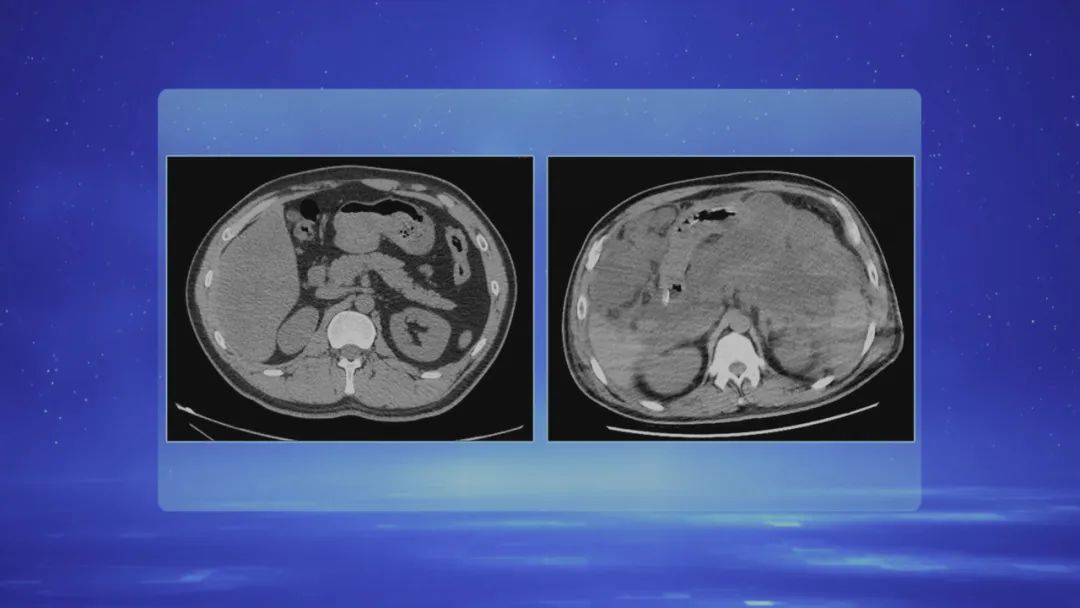

胰腺像一根稍微压扁的香蕉,平时在我们体内存在感很底。但胰腺分泌的胰液有大量的消化酶,可以分解食物的油脂蛋白。而且胰腺非常“智能”,在我们空腹的时候,胰腺就减少或者停止分泌胰液,当我们开始进食,胰腺就得到了信号,开始大量分泌胰液帮助我们消化食物。

胰腺同时影响着人体两种分泌功能,一种是外分泌功能,一种是内分泌功能。很多看上去很常见的生活习惯,都在悄悄的伤害着胰腺。一旦它发出了警报,可能就到了比较严重的情况,甚至出现多器官功能衰竭!更多内容,请关注本期节目。